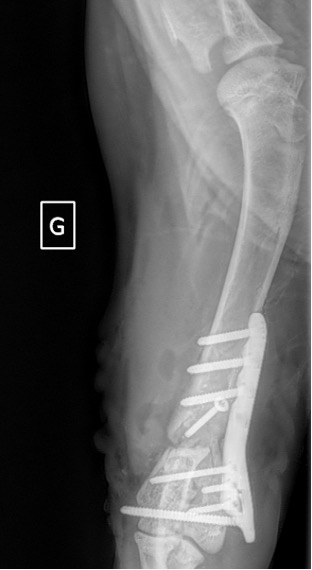

Figure 7 : Post-Op 2 mois

Notre préférence va vers le placement de deux plaques humérales : une médiale de la plus grande taille possible et l’autre latérale, généralement d’une taille inférieure à la première. Dans l’exemple 1 (chat européen), une plaque de 2 mm est utilisée médialement et une plaque de 1,5 mm latéralement. Dans l’exemple 2 (chien Malinois), une plaque de 3,5 mm est utilisée médialement et une plaque de 2,7 mm latéralement.